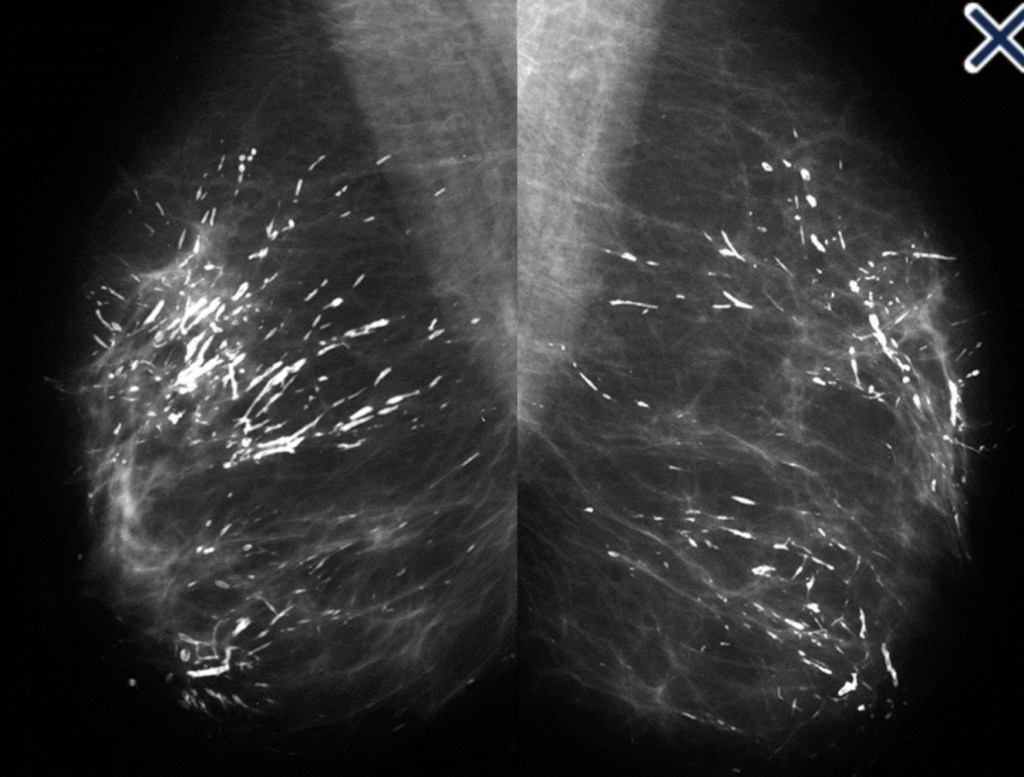

- When coarse rod-like ductal calcifications:

- Are diffuse, bilateral, and not confined to a single lobe:

- They can be confidently assumed to result from plasma cell mastitis:

- They do not require further evaluation or biopsy (Image)

- The process is called secretory disease:

- Because there is a stagnant, viscous fluid that eventually petrifies and results in the smooth contoured calcifications

- Some of them are branching and look like malignant casting type calcifications:

- But the key distinguishing feature:

- Is the diffuse, multilobe, bilateral nature of the process:

- Calcifications become much more worrisome when they are confined to a single lobe